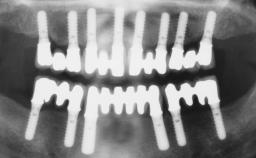

Conventional Loading of Eight Implants in the Maxilla and Final Restoration with a Full-Arch Gold-Ceramic FDP

A 35-year-old Caucasian female presenting with advanced periodontal disease involving both the maxillary and the mandibular dentition was referred for evaluation. The patient, a non-smoker in good general health, requested treatment for recurrent periodontal abscesses, tooth mobility, and discomfort during chewing, as well as restoration of her missing teeth with a fixed prosthesis to improve mastication and esthetics. All residual maxillary teeth exhibited plaque deposits, deep pockets, bleeding on probing, and class III mobility and were evaluated as hopeless. All residual mandibular teeth except tooth 37 could be maintained after periodontal therapy.

| # of Implants | 8 |

| Type of Implants | One-Piece |